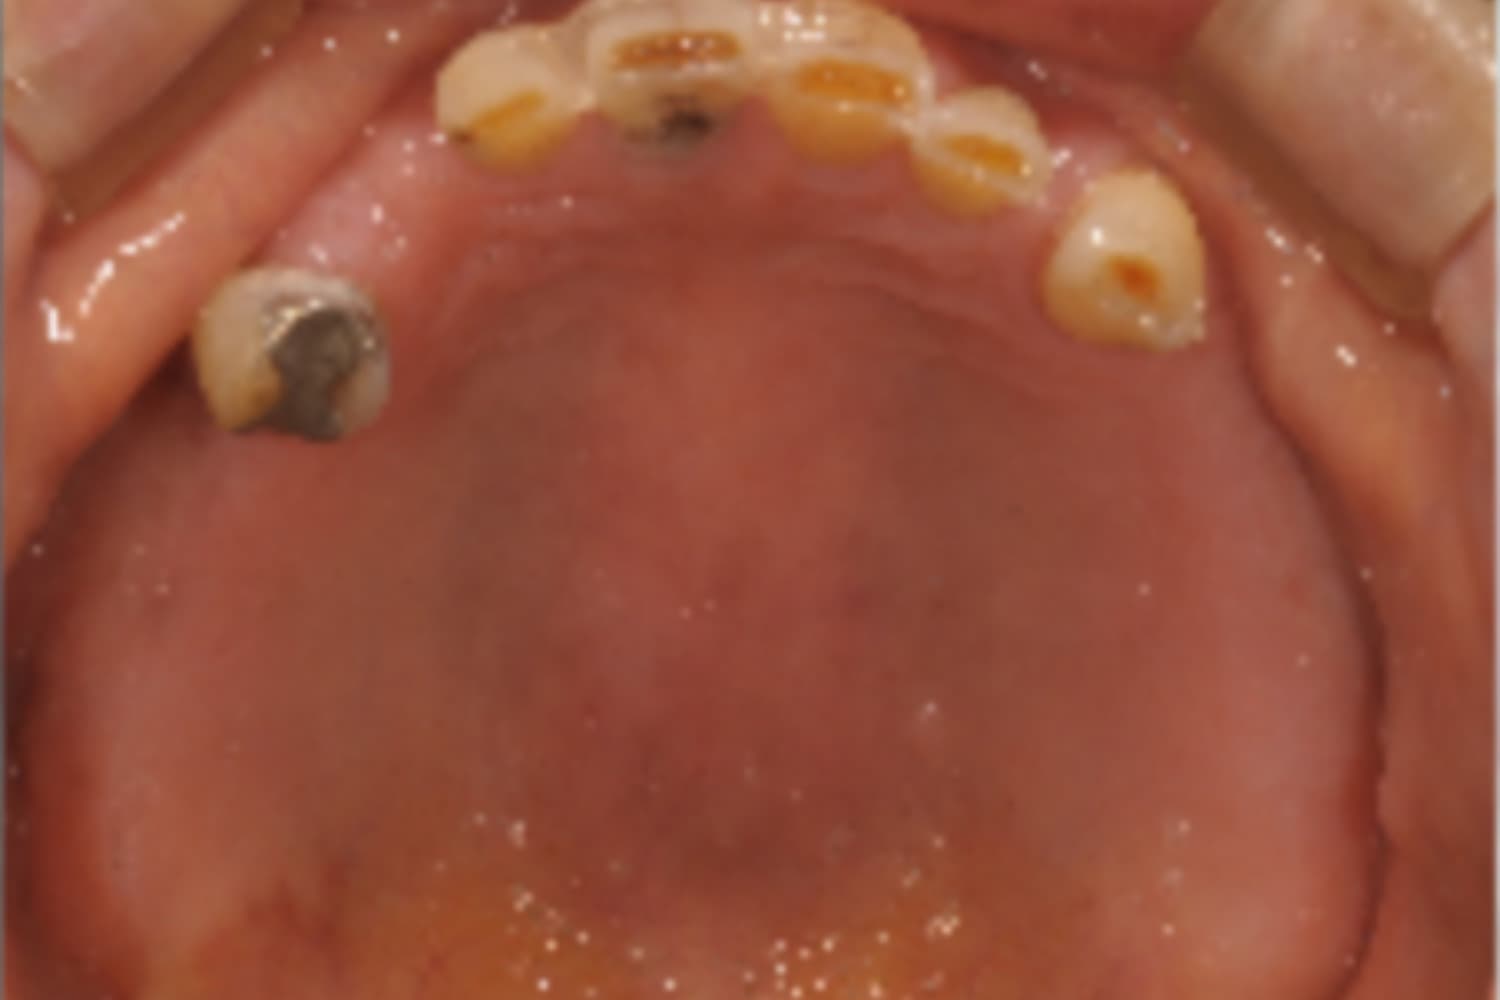

上顎欠損部のインプラント治療

Before

After

上顎欠損部にインプラントを行い、上顎前歯にはセラミックを装着

主訴

物が噛みづらい

治療期間

26カ月

治療回数

26回

費用

3,360,000円

副作用・リスク

・上顎洞炎を発症する可能性がある